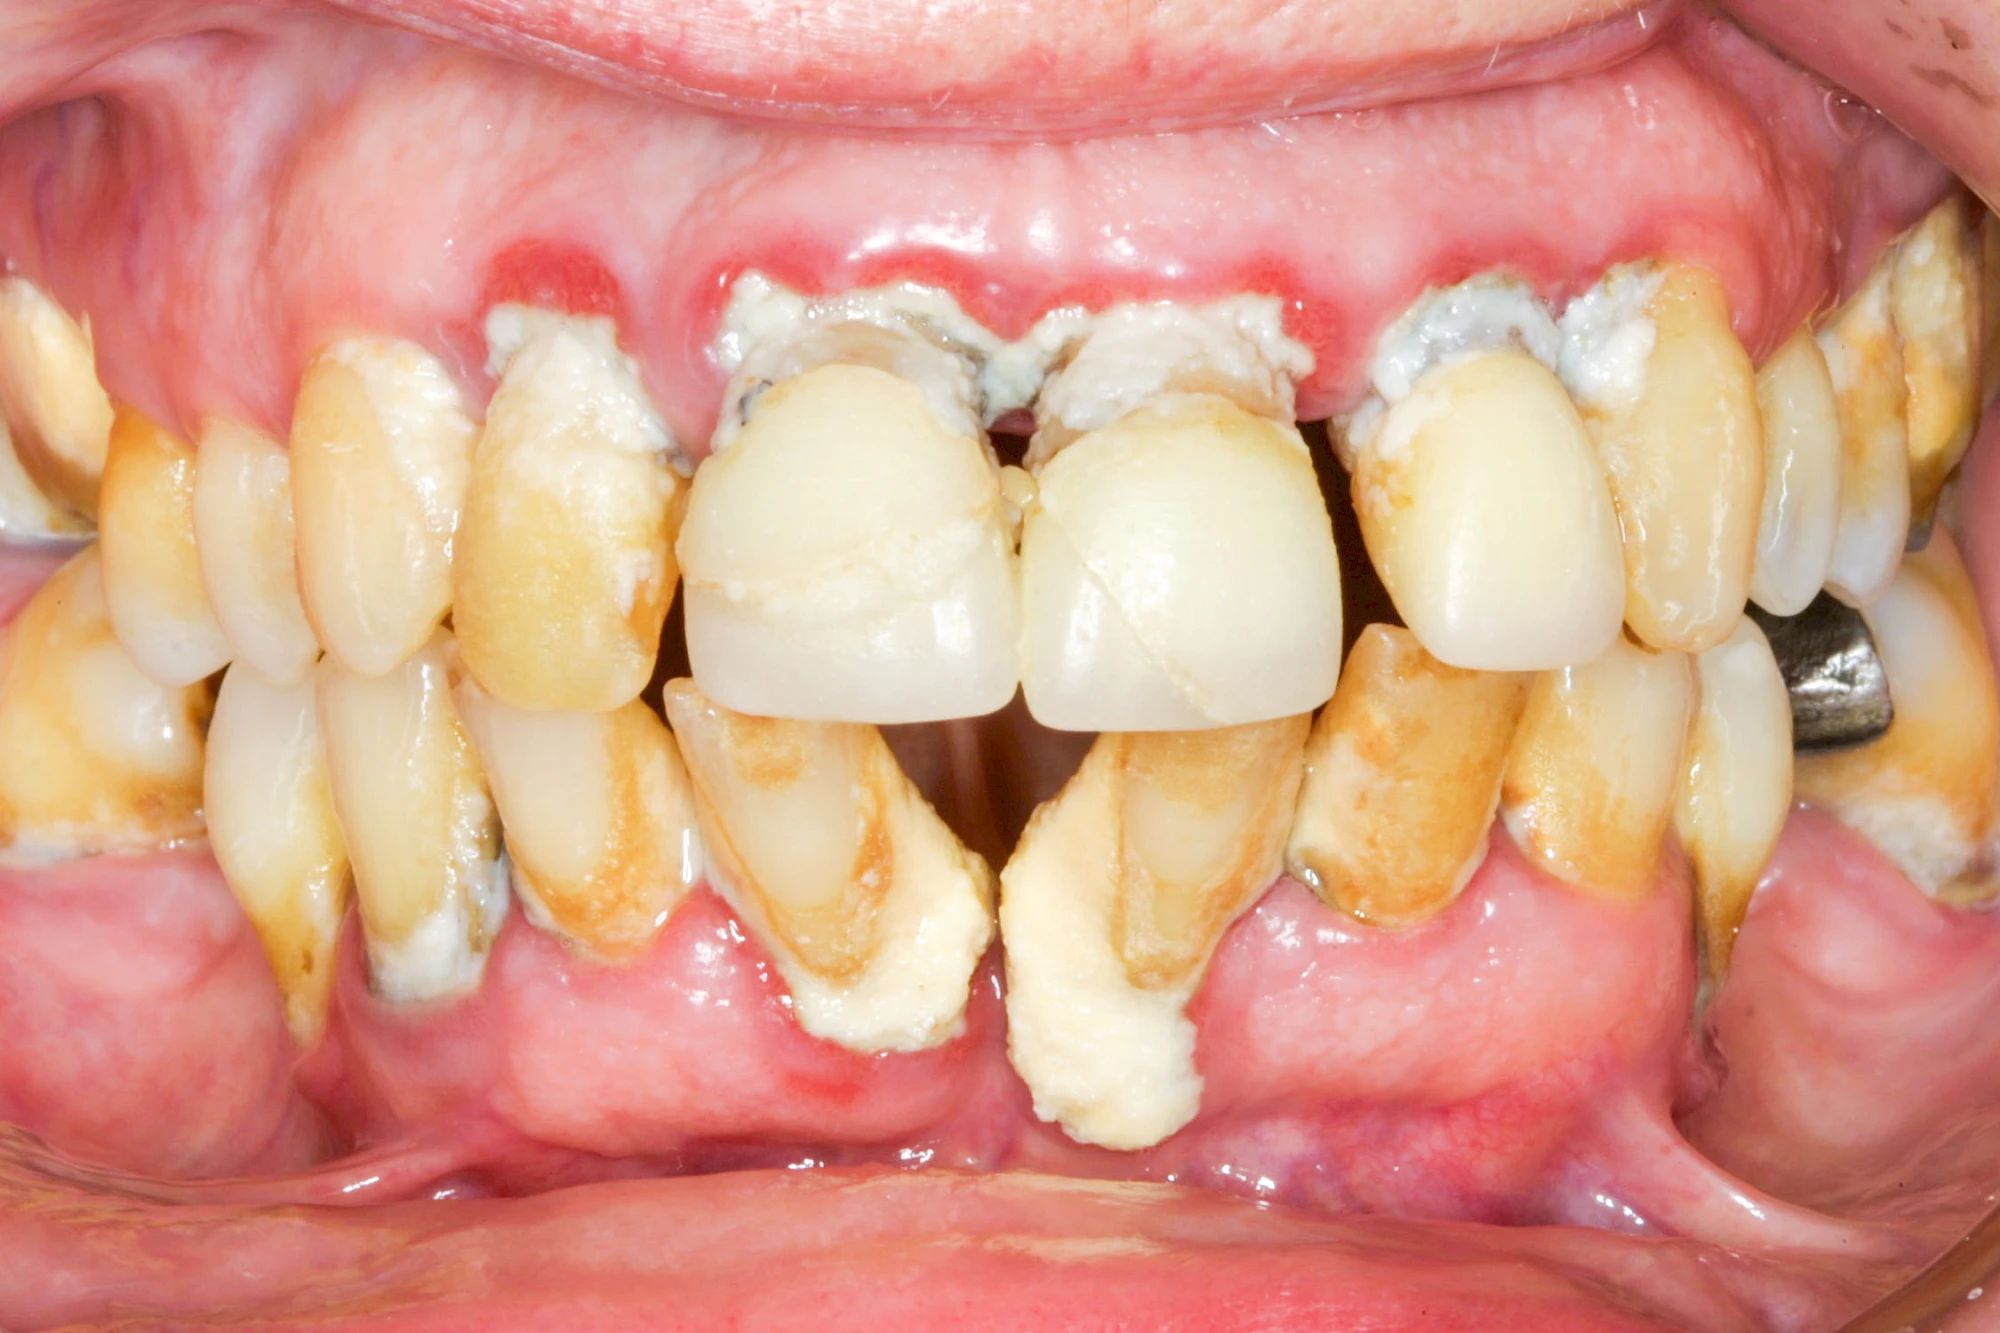

Bakterien in den Zahnbelägen greifen neben den Zähnen auch das Zahnfleisch (Gingiva) und den gesamten Zahnhalteapparat (Parodont) an. Der Körper reagiert mit einer Entzündung, sichtbar als Rötung und Schwellung. Meist blutet das Zahnfleisch z .B. beim Essen oder auch beim Putzen der Zähne.

Ist zunächst nur das Zahnfleisch von der Entzündung betroffen, spricht man von Gingivitis. Später, wenn auch der Knochen um die Zähne herum entzündet ist, spricht man von einer Parodontitis. Bei der Parodontitis wird der Knochen nach und nach abgebaut und das Zahnfleisch zieht sich zurück. Die Zahnhälse und Zahnwurzeloberflächen liegen mehr und mehr frei. Die Zähne werden zunehmend lockerer und fallen schließlich aus.